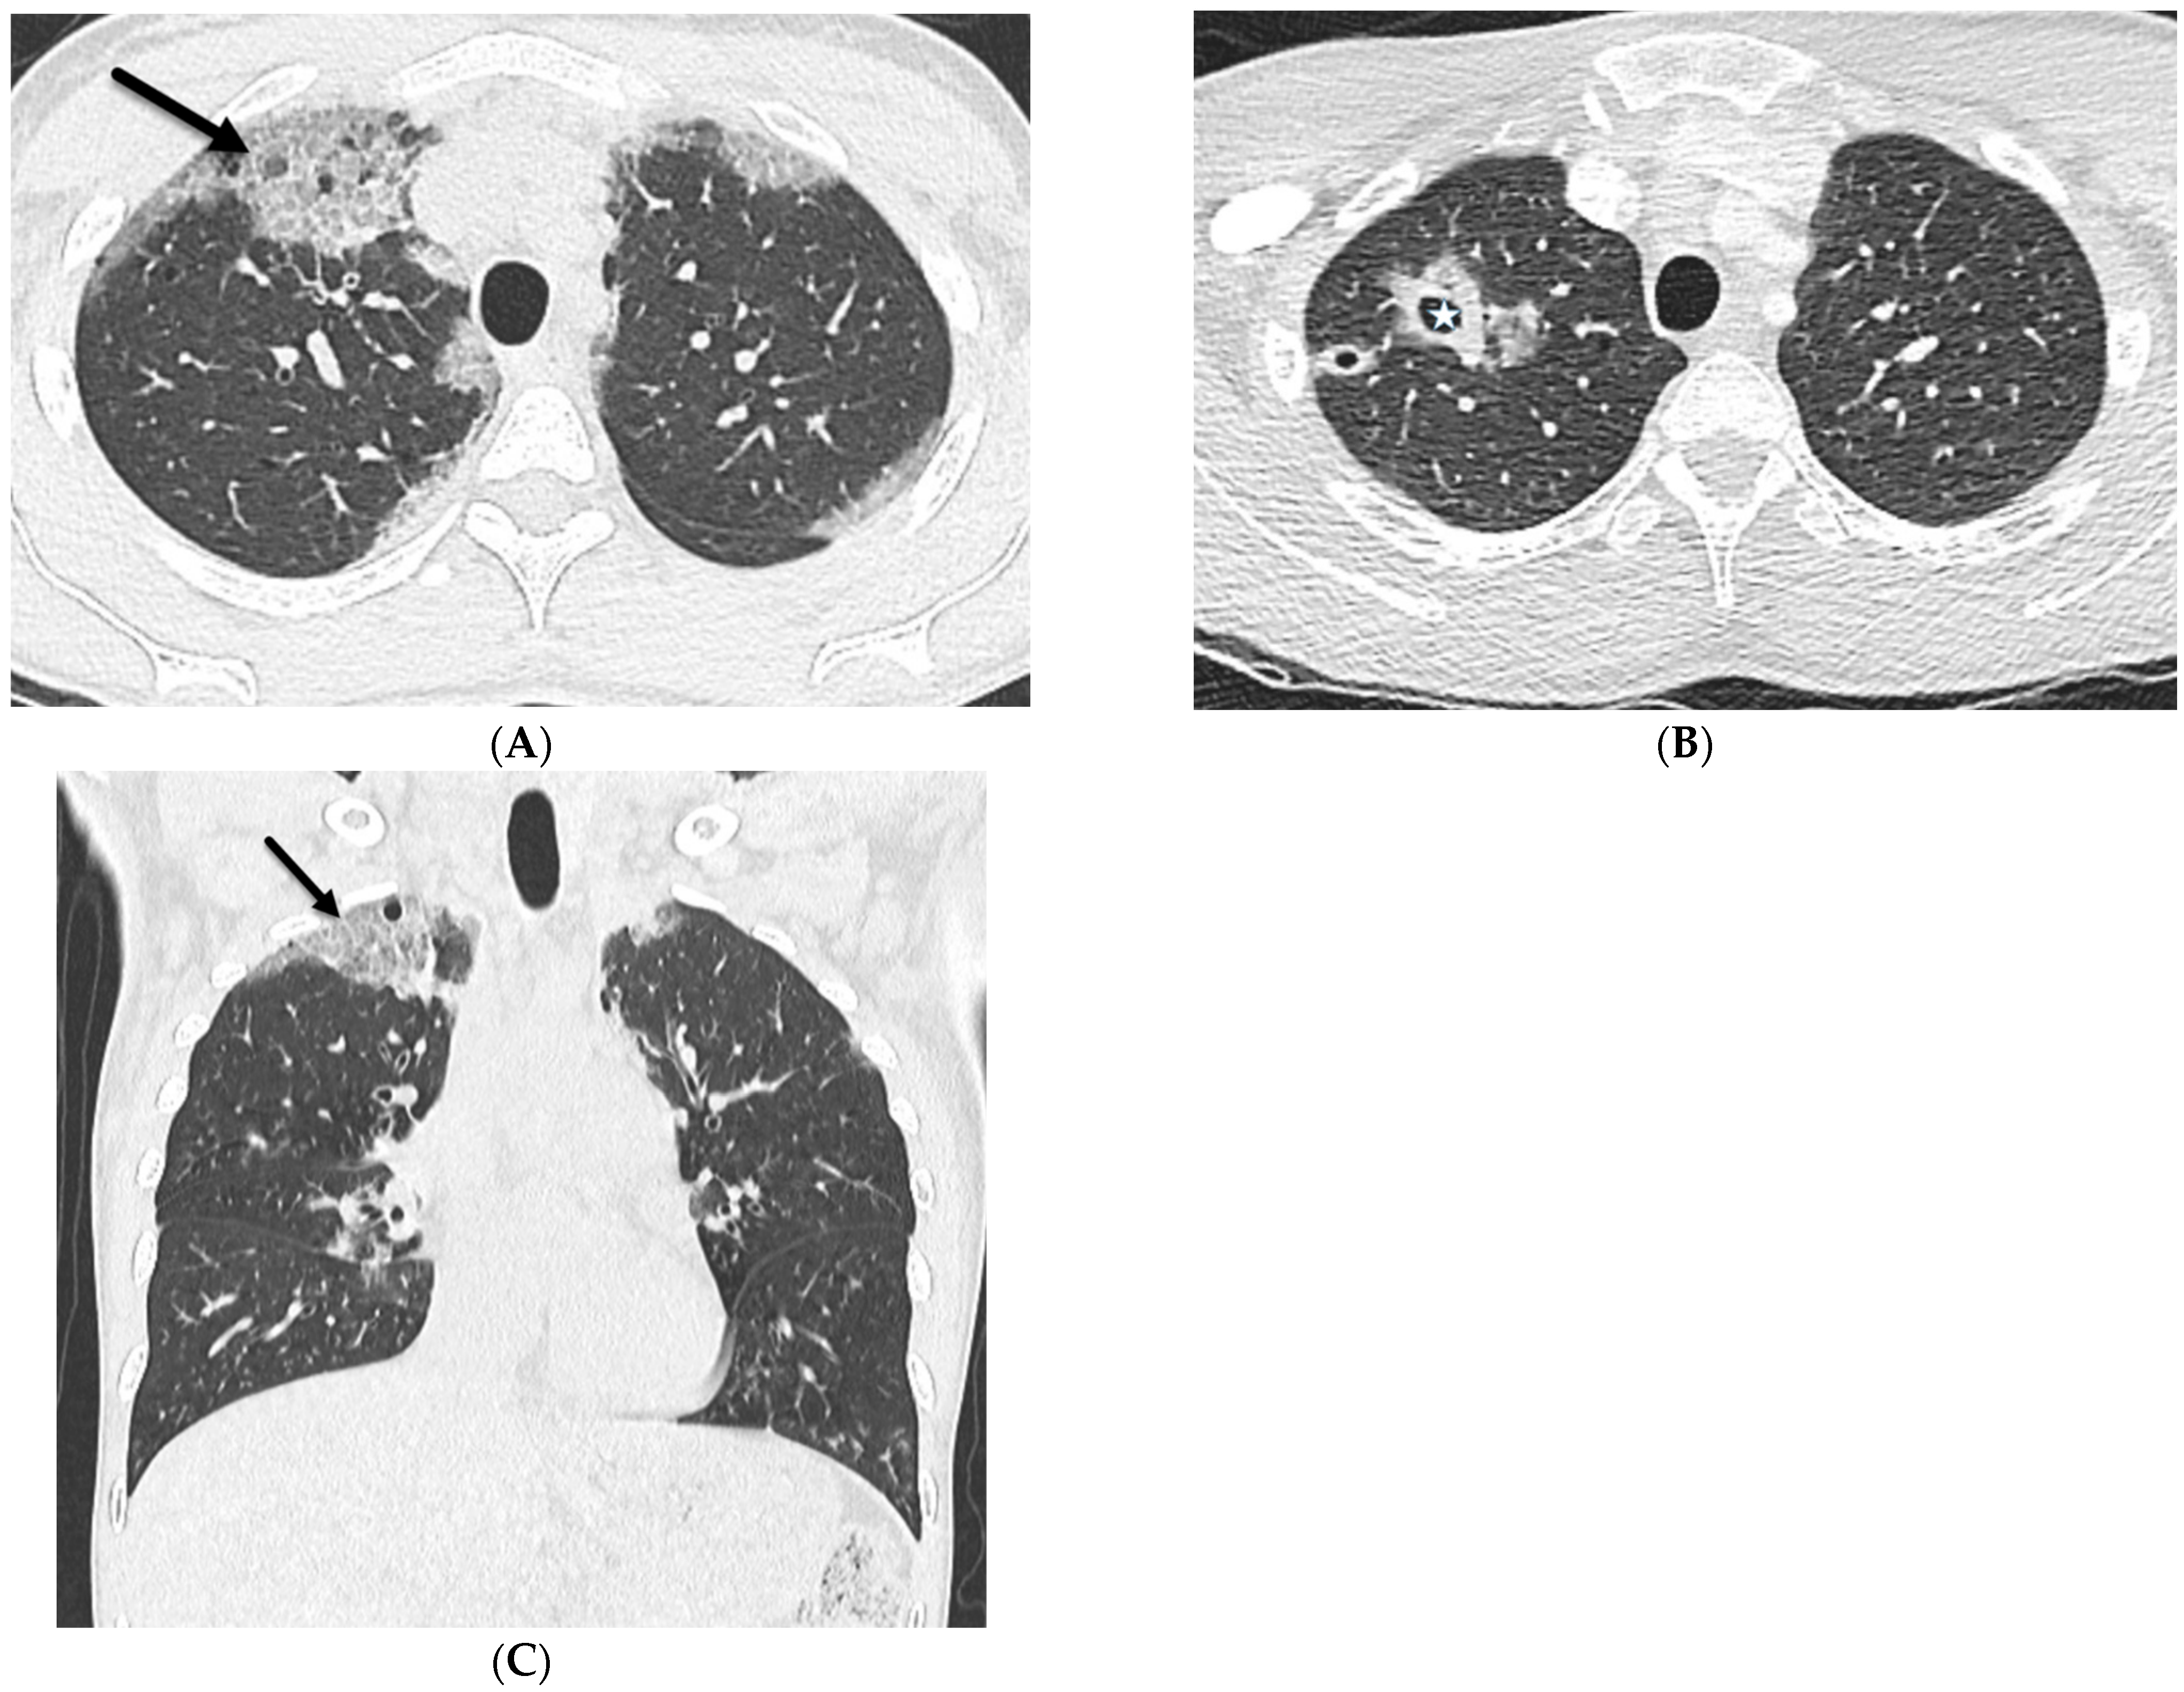

5.2. Kaposi’s Sarcoma

5.3. Lymphoma

5.4. Leukemia